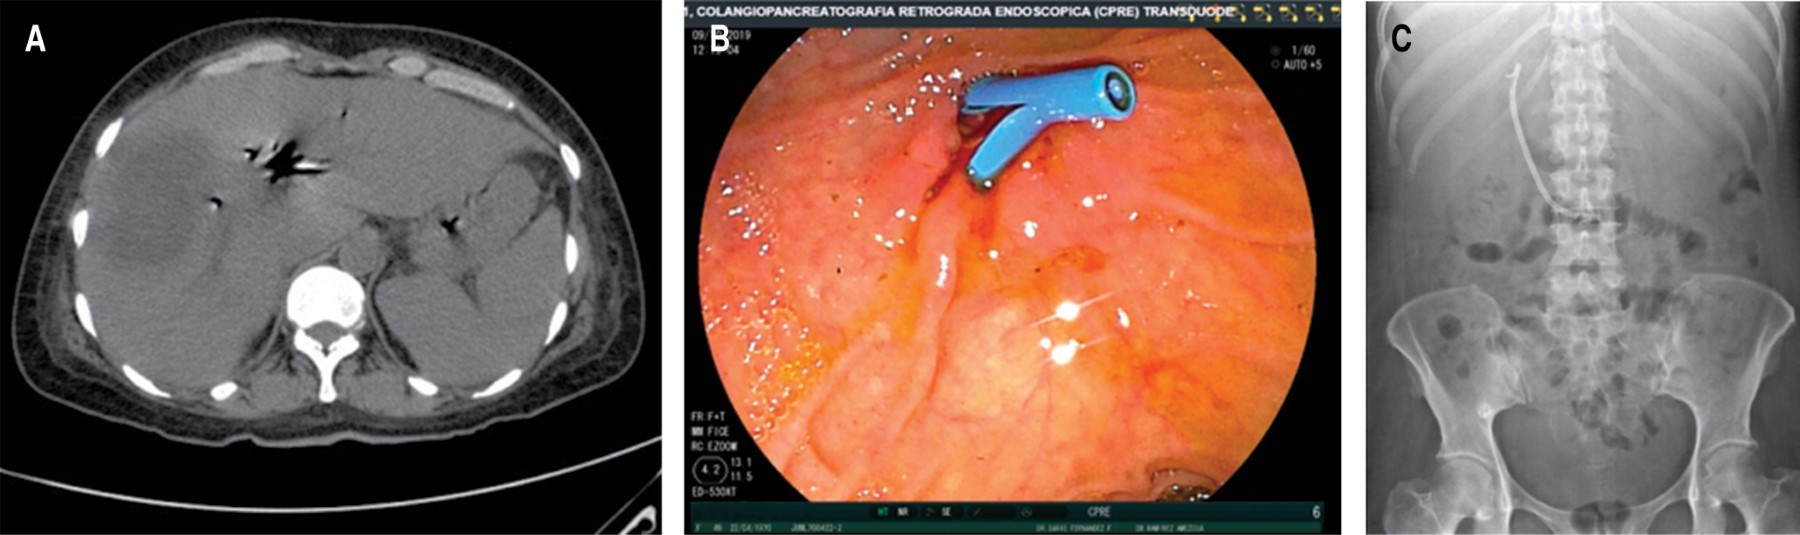

Se le realiza TC abdominal el 02-10-19 que reporta hallazgos de imagen hipodensa de 80 × 53 mm con 23 UH en el segmento VI y VII, en relación con absceso hepático del lado derecho, hepatomegalia a expensas del mismo lóbulo, presencia de neumobilia, la cual aparentemente se observa en comunicación con la pared anterior de la vesícula biliar, escaso líquido libre en hueco pélvico, derrame pleural bilateral y atelectasias pasivas. De igual forma se solicita CPRE el 09-10-19 que reporta colédoco de 6-7 mm, conducto biliar común de 10 mm, se observa defecto de llenado circular de aproximadamente 20 mm que retrasa el vaciamiento del medio de contraste de la vía biliar reportando probable síndrome de Mirizzi tipo IV y fístula bilioentérica de sitio a determinar. Se realiza esfinterotomía, barrido con cánula litotriptora y colocación de endoprótesis tipo Ámsterdam de 10 × 10 cm (Figura 2).

Es enviada a nuestro servicio el 27-10-19, recibiéndola con oximetría de 85% y anasarca, se realiza telerradiografía de tórax a su ingreso que evidencia derrame pleural derecho de 40% aproximadamente, colocándose sello de agua en sexto espacio intercostal con línea media axilar derecha y verificando su colocación con una placa de tórax de control que asegura la colocación de la sonda, planteándose laparotomía exploradora al 29-10-19 (Figura 3).